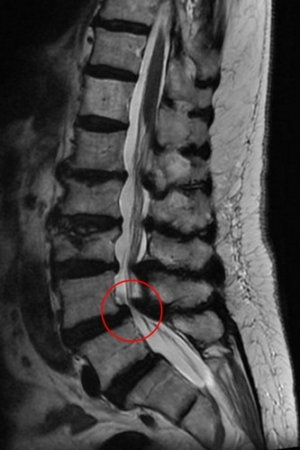

81歲高齡患者脊椎滑脫引發腳痛 經微創手術治療改善生活

來自苗栗縣的81歲的郭奶奶,因腰痛、腿痛和腿麻嚴重影響行走能力,僅能靠輪椅代步,四處求醫無法改善,到花蓮慈濟醫院林欣榮院長門診,經核磁共振造影檢查發現有嚴重脊椎側彎及腰椎滑脫,轉介神經脊椎微創外科主任洪祥益。經謹慎評估風險並與家屬討論後,以微創融合手術治療,患者於術後隔天即可下床,順利擺脫輪椅,重回自如行動的生活。